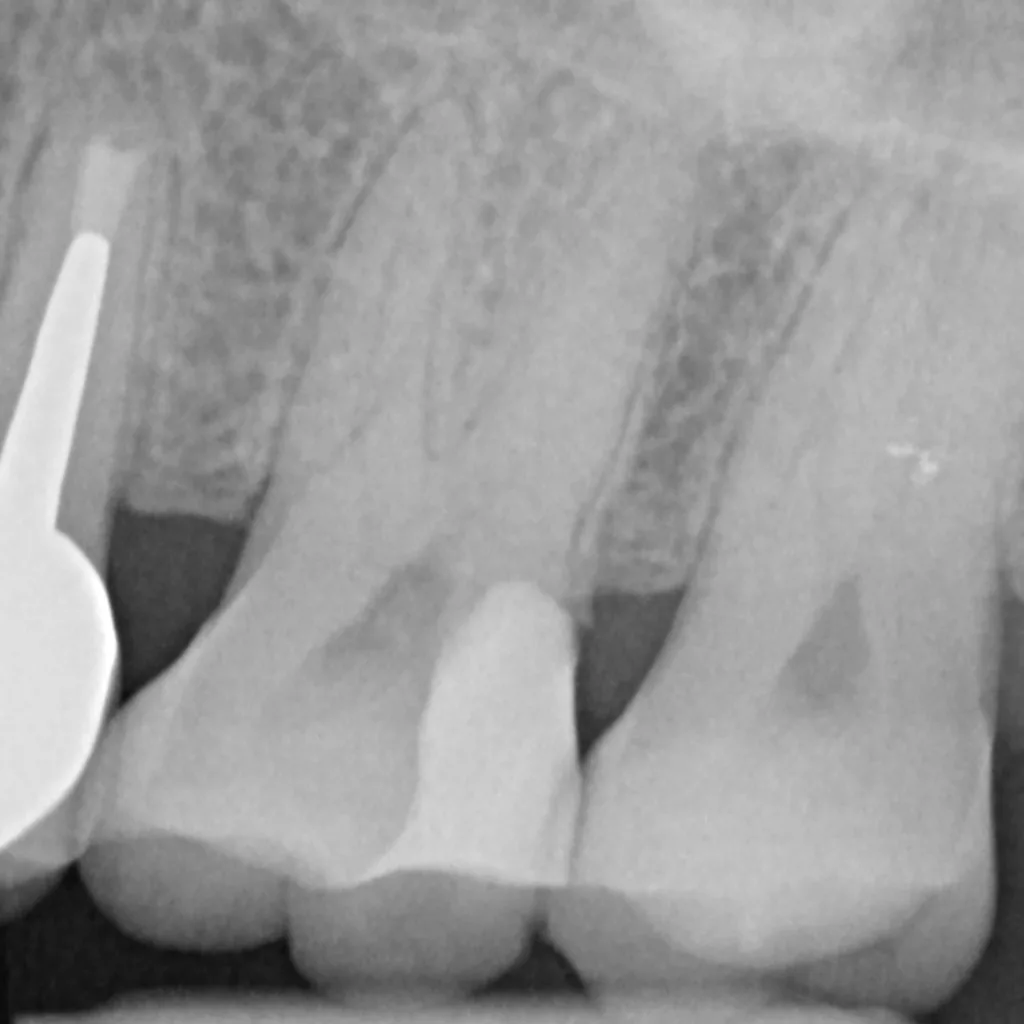

Wird eine profunde kariöse Läsion behandelt, empfiehlt sich folgendes Vorgehen [5]: Zunächst sollte in einem ersten Schritt ein Kofferdam appliziert werden, um eine möglichst keimfreie Arbeitsweise zu gewährleisten. Nach Präparation einer Zugangskavität, wenn dies notwendig ist, erfolgt die Kariesexkavation mittels Rosenbohrern oder Handexkavatoren. Wird in pulpanahen Arealen eine Eröffnung der Pulpa erwartet, sollte das Instrument gewechselt und ein sauberer Rosenbohrer genutzt werden. Tritt nach vollständiger Kariesexkavation keine Eröffnung der Pulpa ein, ist aber von einer dünnen Restdentindicke von etwa 300 µm auszugehen, oftmals erkenntlich durch eine zartrosa hindurchschimmernde Pulpa, sollte nach Kavitätentoilette mittels Natriumhypochlorit (NaOCl) 3% eine indirekte Überkappung mit einem hydraulischen Kalziumsilikatzement erfolgen [5]. NaOCl dient dazu, Bakterien und Toxine zu neutralisieren und das Dentin zu desinfizieren. Die Unterfüllung aus Kalziumsilikatzement soll auch desinfizierend wirken, das Pulpagewebe zur Heilung anregen und vor möglicherweise durch das Dentin penetrierenden Monomeren aus dem Dentinadhäsivsystem schützen [5], da diese die regelrechte Funktion der Odontoblasten beeinträchtigen können [9,40]. Im Anschluss muss eine direkte, dentinadhäsive Restauration zur Versorgung der Kavität platziert werden [5]. Die Abbildungen 1 bis 14 illustrieren das Vorgehen bei der Behandlung einer profunden kariösen Läsion mit indirekter Überkappung der Pulpa.